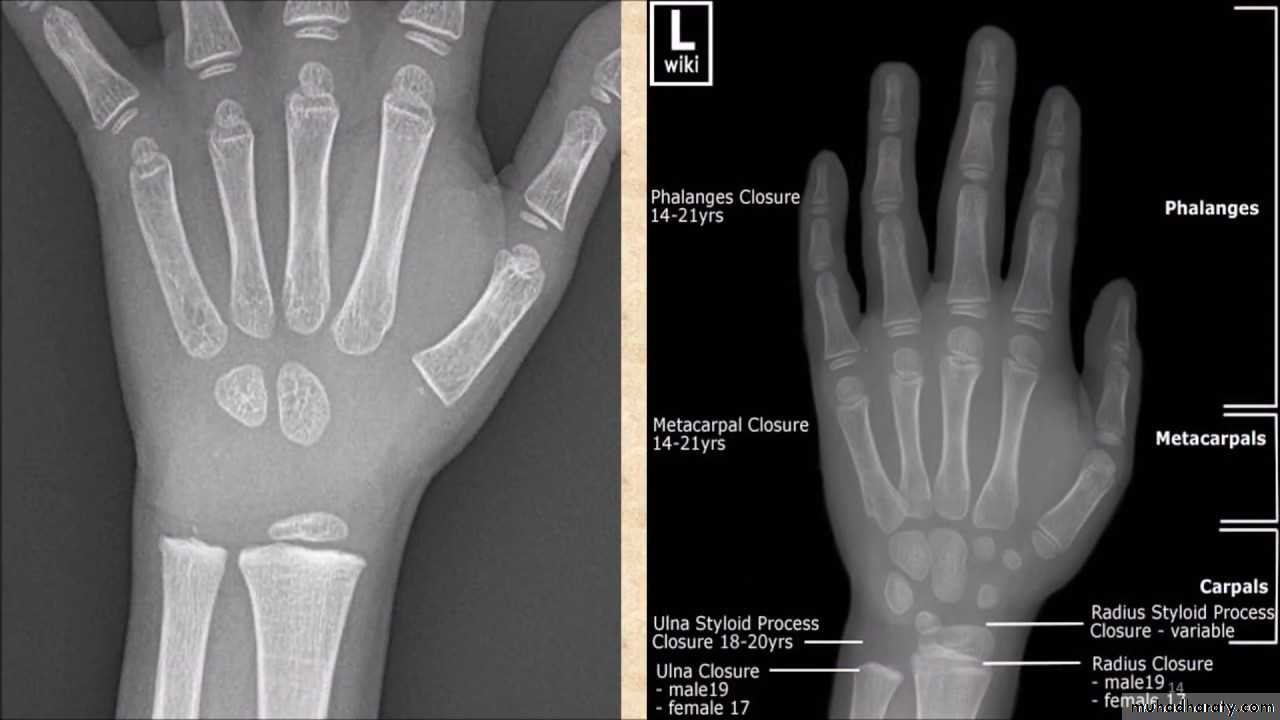

• تقدير العمر من العظام: يستطيع الطبيب ان يقدر العمر بدرجة لاباس بها من الدقة فيما بين الولادة وحتى سن 25 عاما من خلال فحصه المراكزالتعظمية المختلفة وبخاصة تلك التي تظهر في الطرف العلوي, والتي غالبا ما نفضلها على غيرها وذلك لسهولة تحريك الطرف العلوي وبمدى واسع بحيث يتحكم به المصور الشعاعي. يعتمد الطبيب في تقدير العمر على ظهور او التحام مراكز التعظم او كلاهما لمجموعة من العظام, حيث ان هناك اوقات محدد لظهور هذه المراكز والتحامها.

• اثبتت البحوث العلمية ان ظهور المراكز التعظمية والتحامها يحصل في وقت مبكرعند الاناث وفي وقت متاخر عند الذكور بفترة تتراوح بين عدة شهور الى السنة الواحدة. علما ان هذا التطور العظمي قد ينحرف عن مساره الطبيعي في حالة المرض او سوء التغذية اواي عامل اخر يؤثر على النمو.

• عمليا يتم تصوير الرسغ والمرفق والكتف لمن يبدوا ظاهرا دون سن العشرين عاما من العمر. ويصور الحرقف لمن بدا في اواسط العقد الثالث من العمر او اقل, والنهاية الانسية للترقوة والتحام القص بالرهابة لمن تجاوز ذلك.

معدل التحام مراكز التعظم:

1) في سن 13-14 سنة تلتحم البكرة بعمد العضد.

2) في سن 14-15 يلتحم راس الكعبرة بالعمد والنتوء المرفقي بالزند.

3) في سن 16-17 سنة تلتحم اللقمة الانسية بعمد العضد.

4) في سن 17-18 تلتحم النهايتان السفليتان للكعبر والزند كل مع عمده.

5) في سن 18-19 يلتحم راس العضد بعمده.

6) وفي سن 25 سنة يلتحم عرف الحرقف بالحرقف والنهاية الانسية للترقوة بالترقوة.